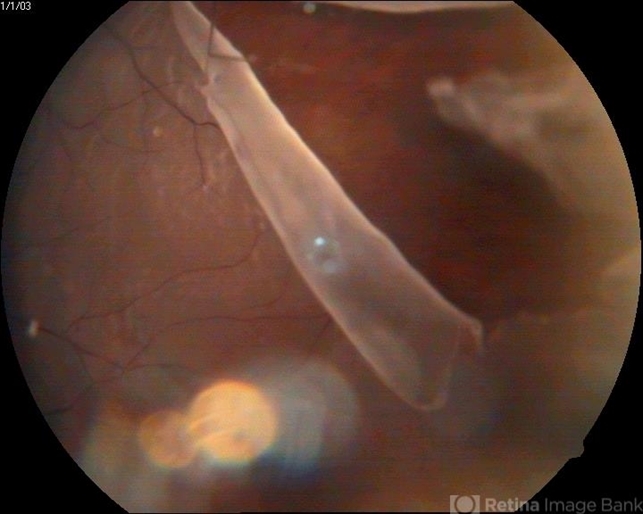

- giant retinal tear

- A myopic male patient 30-years-old presented to outdoor and found to have retinal detachment with giant tear following blunt trauma